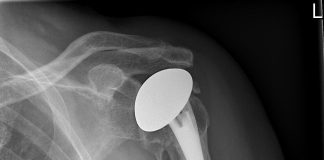

Rijnland Ziekenhuis plaatst eerste schouderprothese uit 3D-printer

Gisteren plaatste dr. Cornelis Visser, orthopeed in Rijnland Ziekenhuis, als eerste in Nederland een totale schouderprothese op maat. Voor de patiënt wordt een unieke mal...